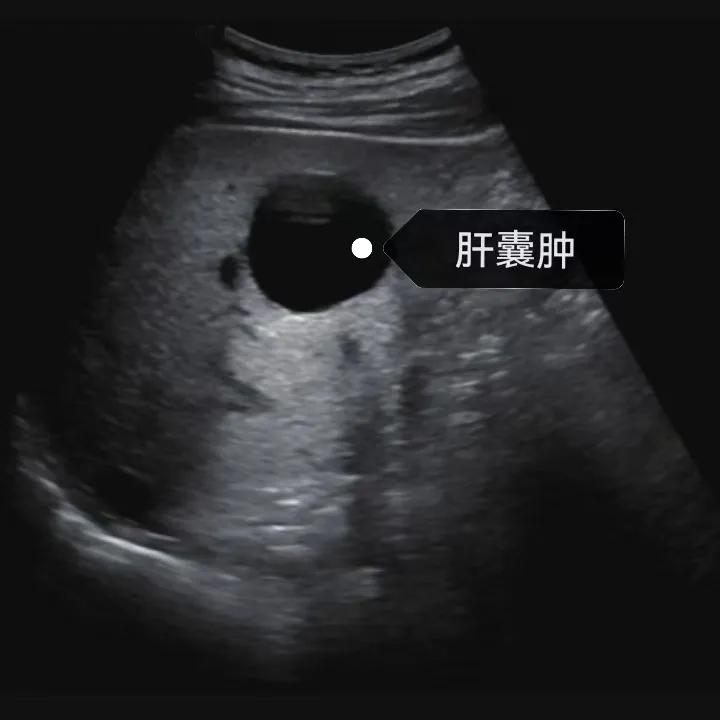

漯河市中醫(yī)院健康科普:認(rèn)識肝囊腫

肝囊腫是一種常見的肝臟良性疾病,呈圓形或橢圓形,外由上皮細(xì)胞包裹形成包膜,內(nèi)由清亮、無色、無細(xì)胞成分的囊液填充,看上去就像是一顆注滿了水的氣球,因此通俗一點(diǎn)說就是肝臟中的“水泡”。

超聲通常是診斷肝囊腫的首選方法,彩超對肝囊腫的檢出率可達(dá)98%,<1cm的囊腫也可檢出。肝囊腫常表現(xiàn)為圓形或橢圓形無回聲,包膜光滑完整,邊界清晰,可有側(cè)壁回聲失落征象,后方回聲增強(qiáng)。病程長、囊腫較大者或囊內(nèi)有過出血、感染者,無回聲腔內(nèi)可見少量絮狀回聲漂浮。超聲對肝囊腫的診斷準(zhǔn)確而靈敏,且方法簡單、無創(chuàng)、費(fèi)用低、可重復(fù)性高,因此常常被作為首選。